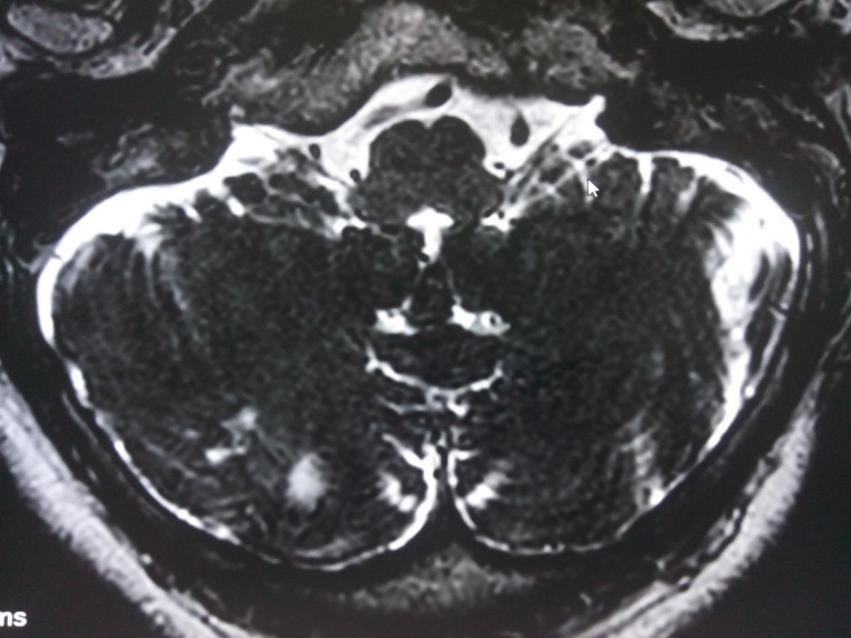

舌咽神经MRTA检查发现同侧椎动脉及小脑后下动脉压迫舌咽及迷走神经